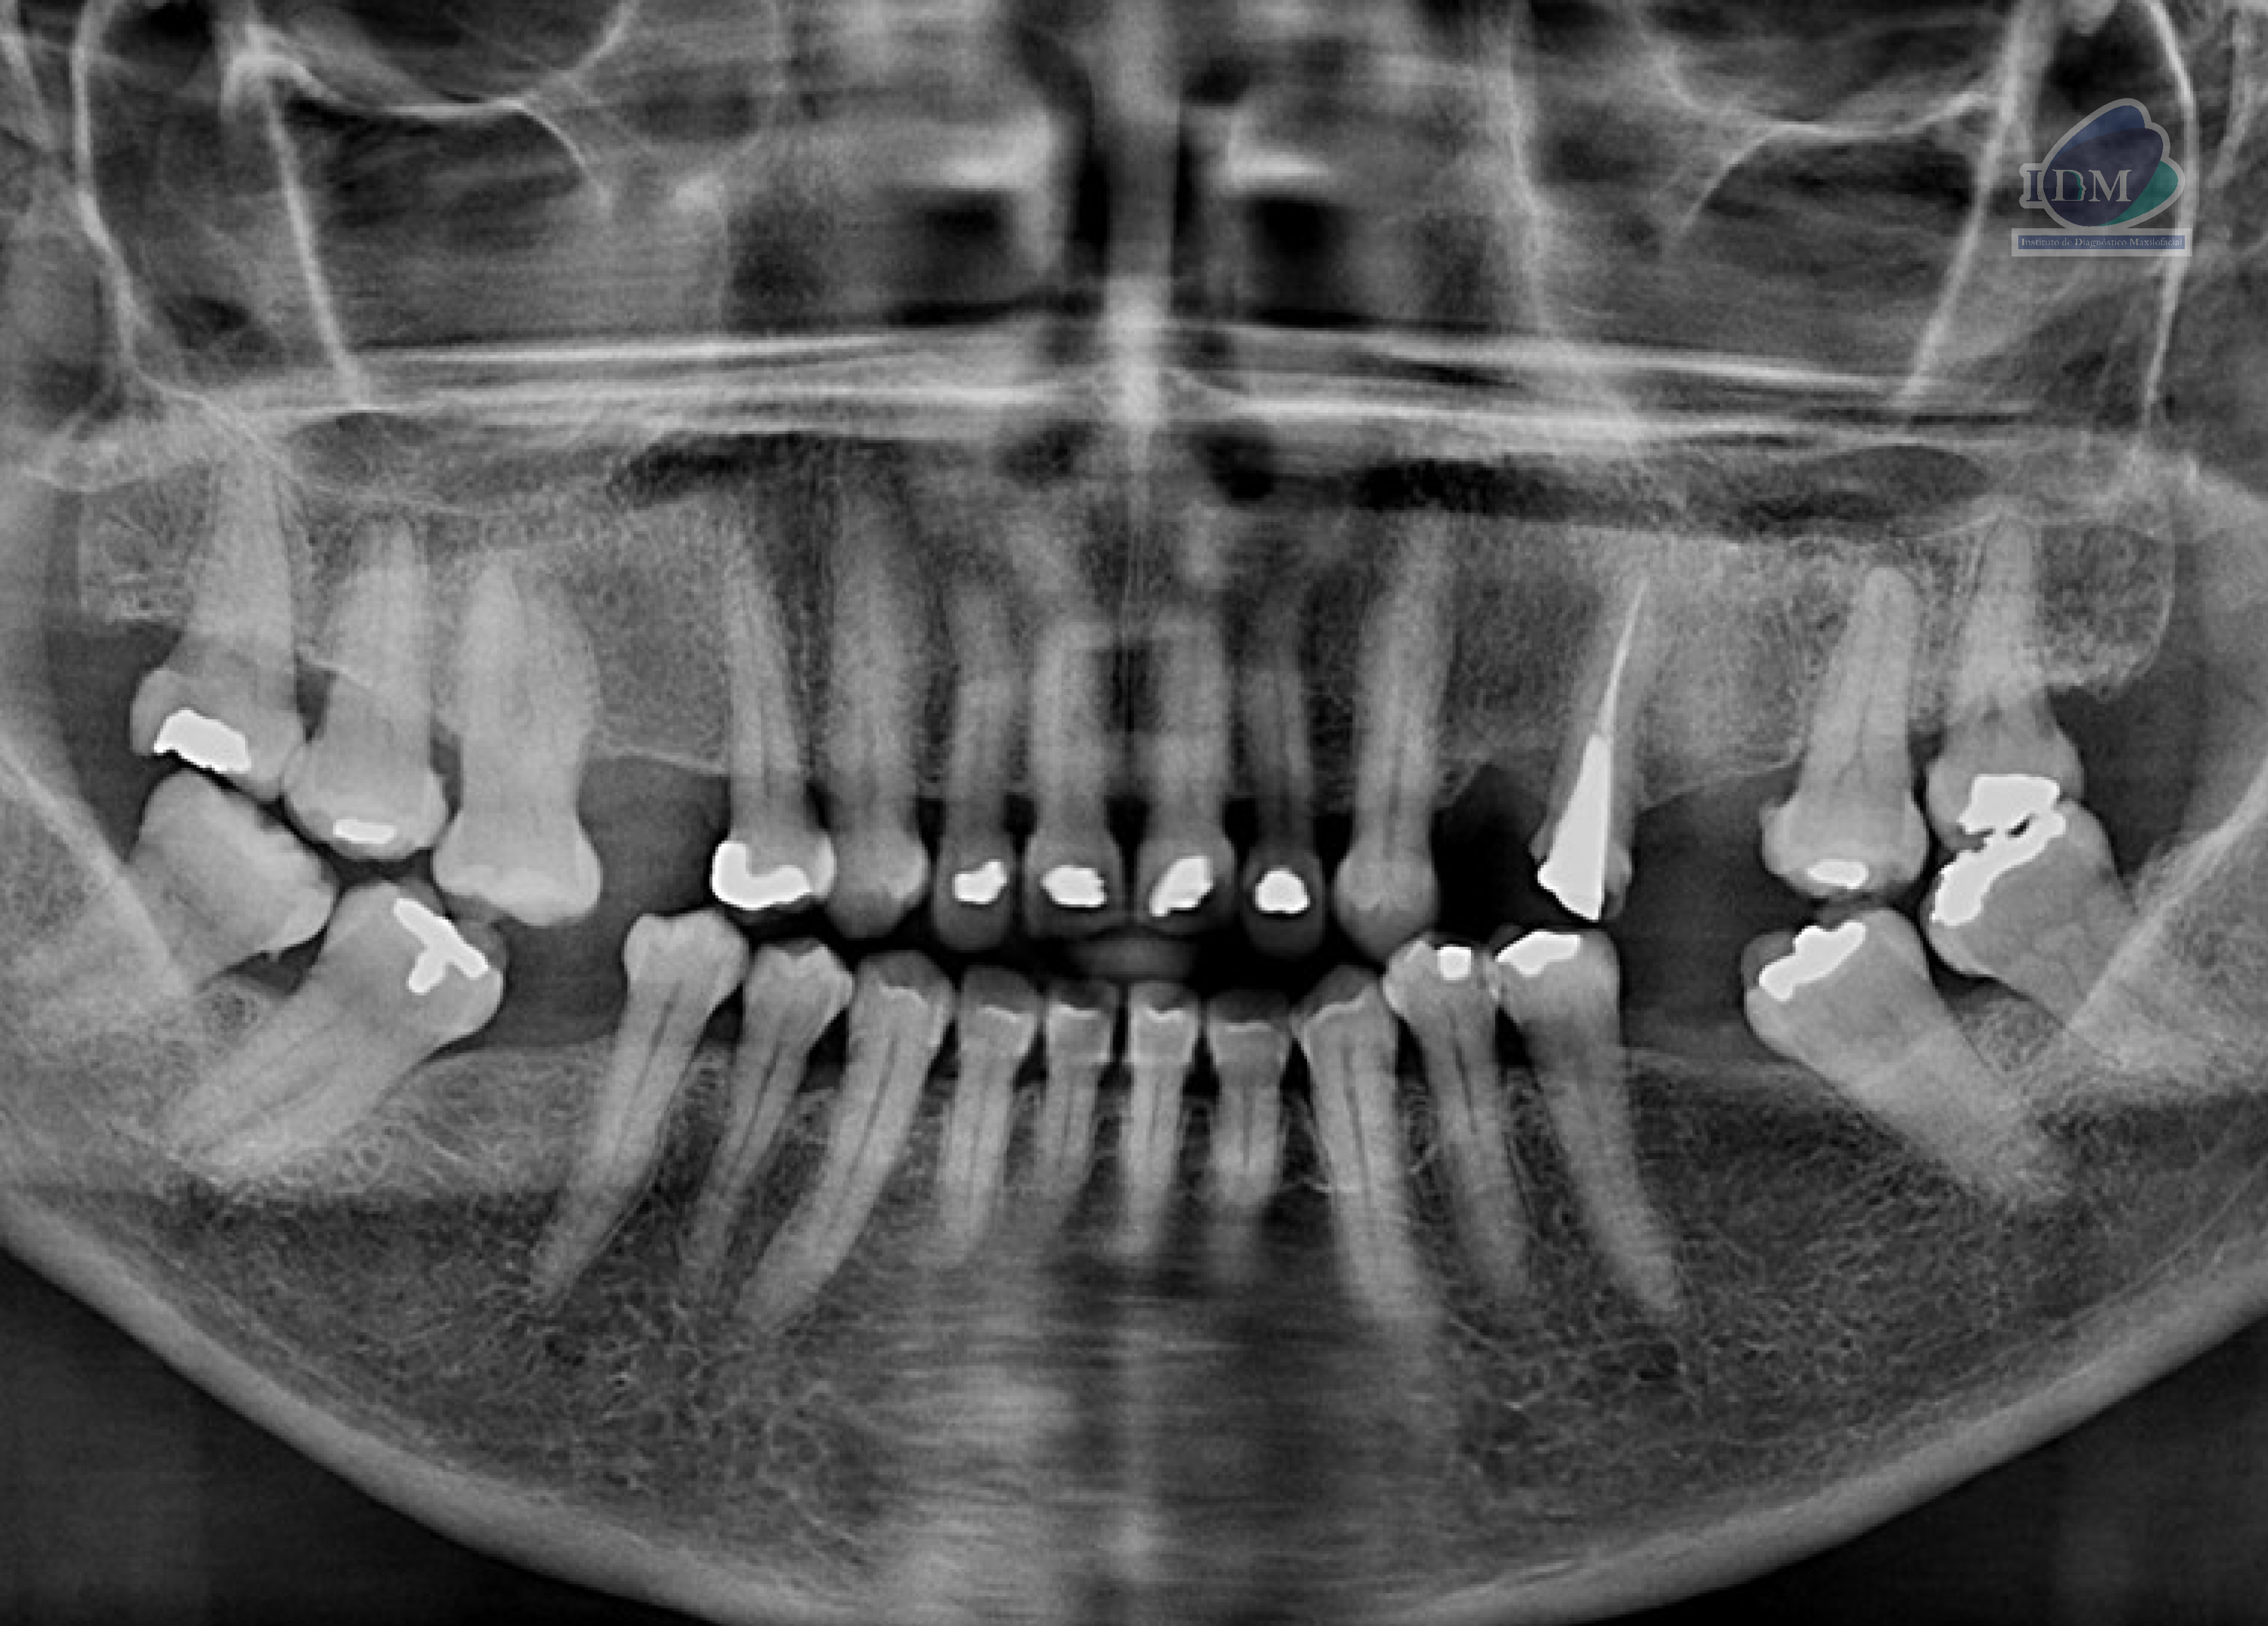

Paciente femenina de 56 años acude para evaluación de senos paranasales. A la evaluación de radiografía panorámica se observa aplanamiento del contorno condilar bilateral. La neumatización alveolar de ambos senos maxilares, múltiples restauraciones coronarias, placa cervical mineralizada y reabsorción ósea moderada del proceso alveolar.

Radiografia Panorámica